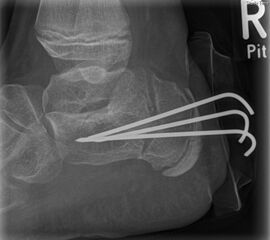

Zusätzlich schränken Wachstumsfugen die Wahl der Osteosynthese ein. Eine die Fuge kreuzende Osteosynthese ist ausschließlich mit Kirschner-Drähten möglich (Abb. 3).

Abb. 3 a-j: Beispiel einer Calcaneusverschiebeosteotomie mit offenen Wachstumsfugen und der entsprechenden Osteosynthese mit Kirschner Drähten. Lokalisation der Osteotomie (a), Lage der Fräse (b-d), Drahtlage mehrere Ansichten (e-h), Heilung der Osteotomie 4 Wochen postoperativ und Entfernung der Drähte (i-j).

Calcaneus-Osteotomie

Die minimalinvasive Calcaneusverschiebeosteotomie bietet eindeutige Vorteile gegenüber dem offenen Verfahren, sodass wir bei Kindern und Jugendlichen nahezu keine offene Verschiebeosteotomie mehr durchführen. Am Calcaneus liegt die offene Wachstumsfuge dorsal. Bei der Durchführung müssen Schenkel der V-förmigen Osteotomie daher etwas steiler angelegt werden, in einem stumpfen Winkel (siehe Abb. 3 a-j). Für die Osteotomie liegen unsere Patienten auf dem Rücken und der BV wird für die exakte Seitaufnahme eingestellt. Der Fuß lagert auf einem hohen OP-Kissen und die Osteotomie kann bequem mit einem langen Kirschner-Draht und einem sterilen Stift angezeichnet werden (Abb. 15).